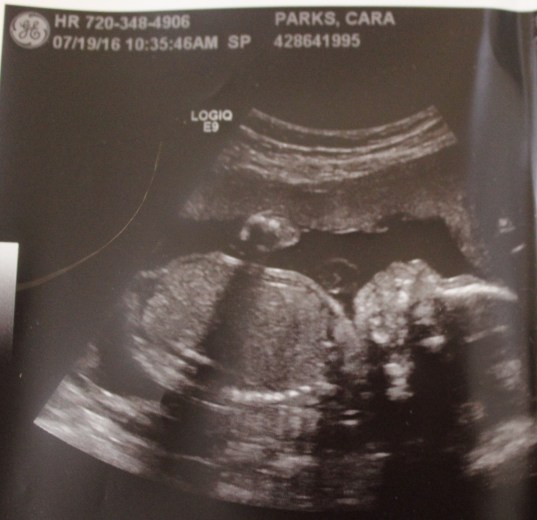

Best moment this week: Really getting started on the Nursery! The paint is finished and I have started to buy decor items and I’m ready to get it all set up and all put together for baby girl! Also, having our ultrasound and seeing our baby girl! They measured her legs and she has long legs already, just like her daddy!

Our Little Princess. Those are her hands on her tummy.